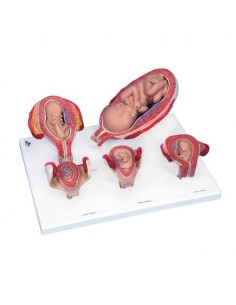

Dal cranio in 22 parti con incastri magnetici ai modelli di colonna vertebrale, da quelli di articolazioni a quelli di cuore, ogni pezzo della nostra collezione è progettato per un’immersione totale nello studio dell’anatomia umana. I nostri modelli, realizzati tramite scansioni di ossa vere, garantiscono un’esperienza tattile autentica e una fedeltà di peso quasi identica agli originali.

Essenziali per studenti e professionisti, i nostri modelli anatomici sono strumenti didattici che permettono di osservare le strutture anatomiche con precisione, eliminando la necessità di dissezioni o studi invasivi. Sono inoltre utili per spiegare ai pazienti le patologie, rendendo la comunicazione più efficace e risparmiando tempo prezioso.